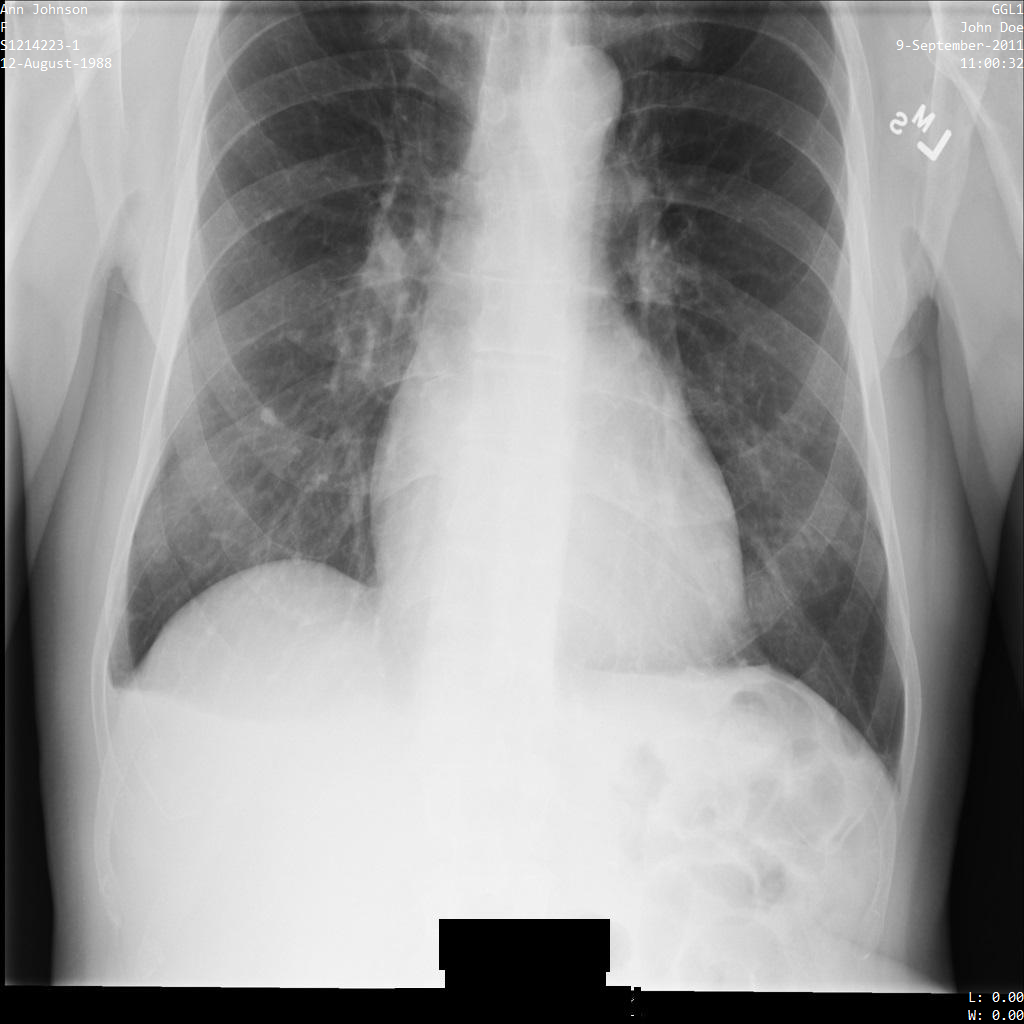

以下各部分提供的示例展示了如何使用各种方法对 DICOM 数据进行去标识化。每个示例都会提供去标识化后的图片输出。每个示例都使用以下原始图片作为其输入:

您可以将每个去标识化操作的输出图片与该原始图片进行比较,以查看该操作的效果。

将图片提交到 Cloud Healthcare API 后,图片显示如下。虽然图片顶部角落显示的元数据已被遮盖,但图片底部的烧屏受保护健康信息 (PHI) 仍然保留。如需一并移除烧屏文字,请参阅遮盖图片中的烧屏文字。

将图片提交到 Cloud Healthcare API 后,图片显示如下。除了 removelist 中提供的标记之外,便只有 PatientBirthDate 会从图片中移除,因为它是 removelist 中唯一与图片中可见的元数据对应的标记。

虽然图片顶部角落的 PatientBirthDate 已根据 removelist 中的配置进行了遮盖,但图片底部的烧屏 PHI 仍会保留。如需一并移除烧屏文字,请参阅遮盖图片中的烧屏文字。

使用 ATTRIBUTE_CONFIDENTIALITY_BASIC_PROFILE 标记过滤条件配置文件将图片提交到 Cloud Healthcare API 后,图片显示如下。虽然图片顶部角落显示的元数据已被遮盖,但图片底部的烧屏 PHI 仍会保留。如需一并移除烧屏文字,请参阅遮盖图片中的烧屏文字。